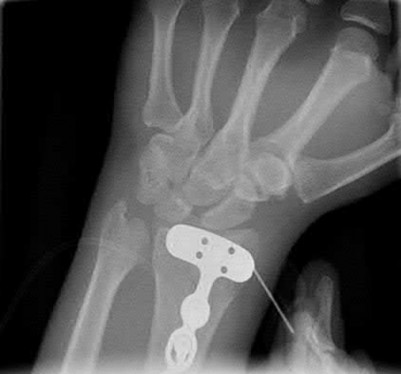

A 51-year-old female presents with an acute inability to extend her thumb, four months after she was treated with cast immobilization for a minimally-displaced distal radius fracture. What is the most appropriate treatment at this time?

A rare complication of non-displaced or minimally displaced fractures of the distal radius treated with a cast is a delayed rupture of the extensor pollicis longus (EPL) tendon. The EPL is the primary extensor of the interphalangeal joint of the thumb and also assists with metacarpophalangeal extension.

Extensor indicis proprius transfer to the EPL is the most widely used and reported treatment for this condition.

Magnussen et al. reviewed results of EIP transfer following ruptures of the EPL, with 19/21 good results. None of the cases had any loss of independent index finger extension although index extensor strength reduced to half of that of the contralateral side.

Hove et al. reported a similar satisfaction rate following treatment of 15 patients. In his series of 4,400 distal radius fractures treated over a 5 year period, the incidence of delayed tendon rupture following distal radius fracture was 0.3 percent.